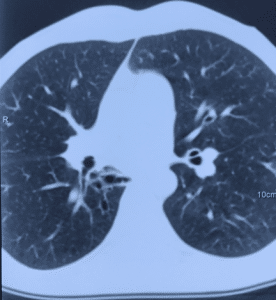

- Мультиспиральная компьютерная томография шеи, органов грудной клетки и/или брюшной полости для обнаружения зоны свища, скоплений жидкости, оценки степени поражения легочной паренхимы, плевральной полости и средостения (рисунок 3).

Вторичные бронхоэктазы и пневмофиброз нижней доли правого легкого у пациента с пищеводно-бронхиальным свищом и тотальной ожоговой стриктурой пищевода.